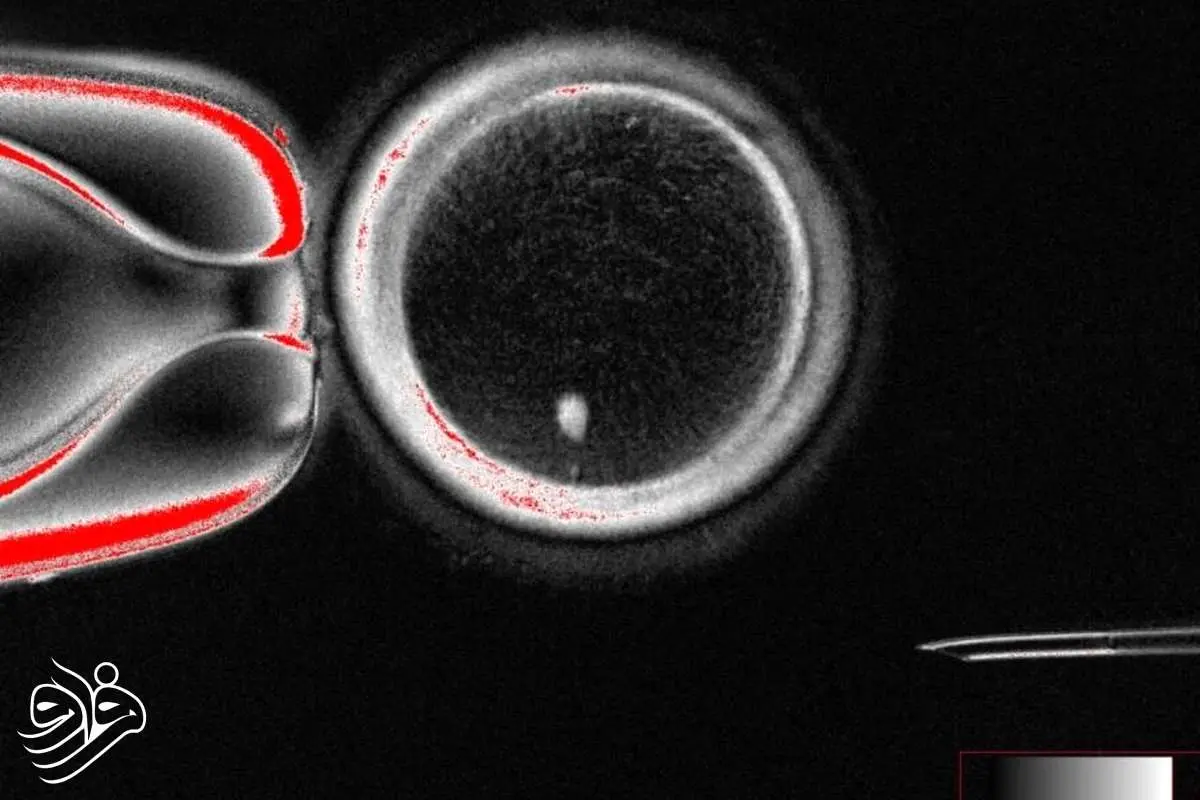

به گزارش خبرگزاری فارس، شوخرات میتالیوپ از دانشگاه اورگان و تیمش با استفاده از تکنیک انتقال هسته سلول سوماتیک (somatic cell nuclear transfer) سلولهای پوستی زنان را برداشتند و هسته آنها را به تخمک اهداکنندهای که هسته خود را از دست داده بود منتقل کردند. هسته سلول حاوی ۴۶ کروموزوم است که کد ژنتیکی انسان را تشکیل میدهد.چالش اصلی دانشمندان این بود که تخمک سالم انسان تنها ۲۳ کروموزوم دارد و برای تشکیل جنین، ۲۳ کروموزوم دیگر از اسپرم لازم است. با استفاده از ترکیبی به نام روسکوویتین (roscovitine)، تیم اورگان توانست نیمی از کروموزومهای اضافی را به یک ساختار موسوم به «بدن قطبی» منتقل کند تا کروموزومهای باقیمانده با اسپرم جفت شوند.

با این حال، در تخمکهای تولیدشده کروموزومها به صورت تصادفی جفت شدند و بسیاری از جنینها دارای تعداد یا ترکیب نادرست کروموزومها بودند. این بدان معناست که هنوز تخمکها برای ایجاد نوزاد سالم آماده نیستند و تیم تحقیقاتی در حال بهبود روش است.از ۸۲ تخمک تولیدشده، کمتر از ۱۰ درصد به مرحلهای رسیدند که معمولاً در IVF به رحم مادر منتقل میشوند و هیچکدام بیش از شش روز کشت نشدند.